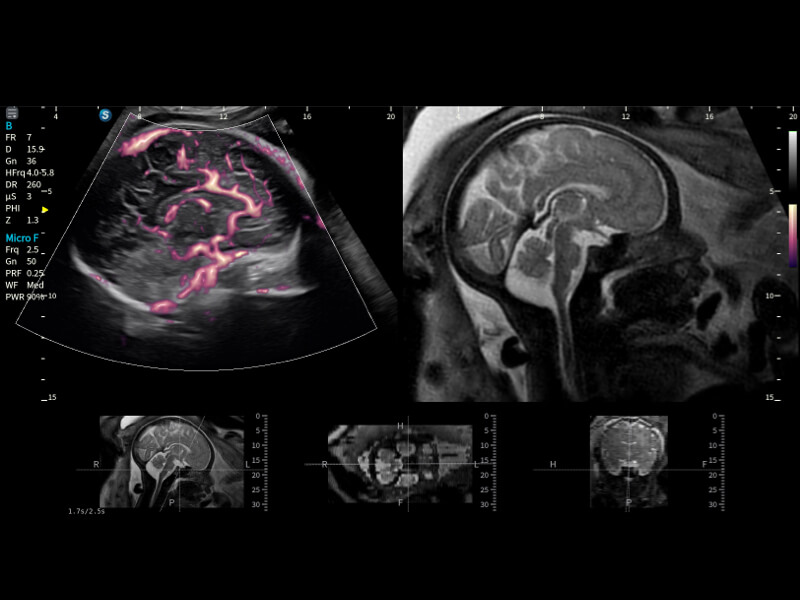

通过创新的Matrix E自适应滤波算法,能有效滤除软组织和噪声信号,最大限度保留超低速微细血流的信号;结合超长时间域算法,极大提升细微血流的敏感性和空间分辨率,更真实的反应组织、包块的血流灌注情况。

作为开立医疗全新打造的超高端旗舰超声产品,从探头抬起唤醒开启扫查到多维探头发射接收,通过先进的场成像发射、自适应聚合重建等技术,基于RF Data原始射频数据在图像生成、高端功能等方面实现突破,为妇产科、儿科提供全方位临床解决方案。